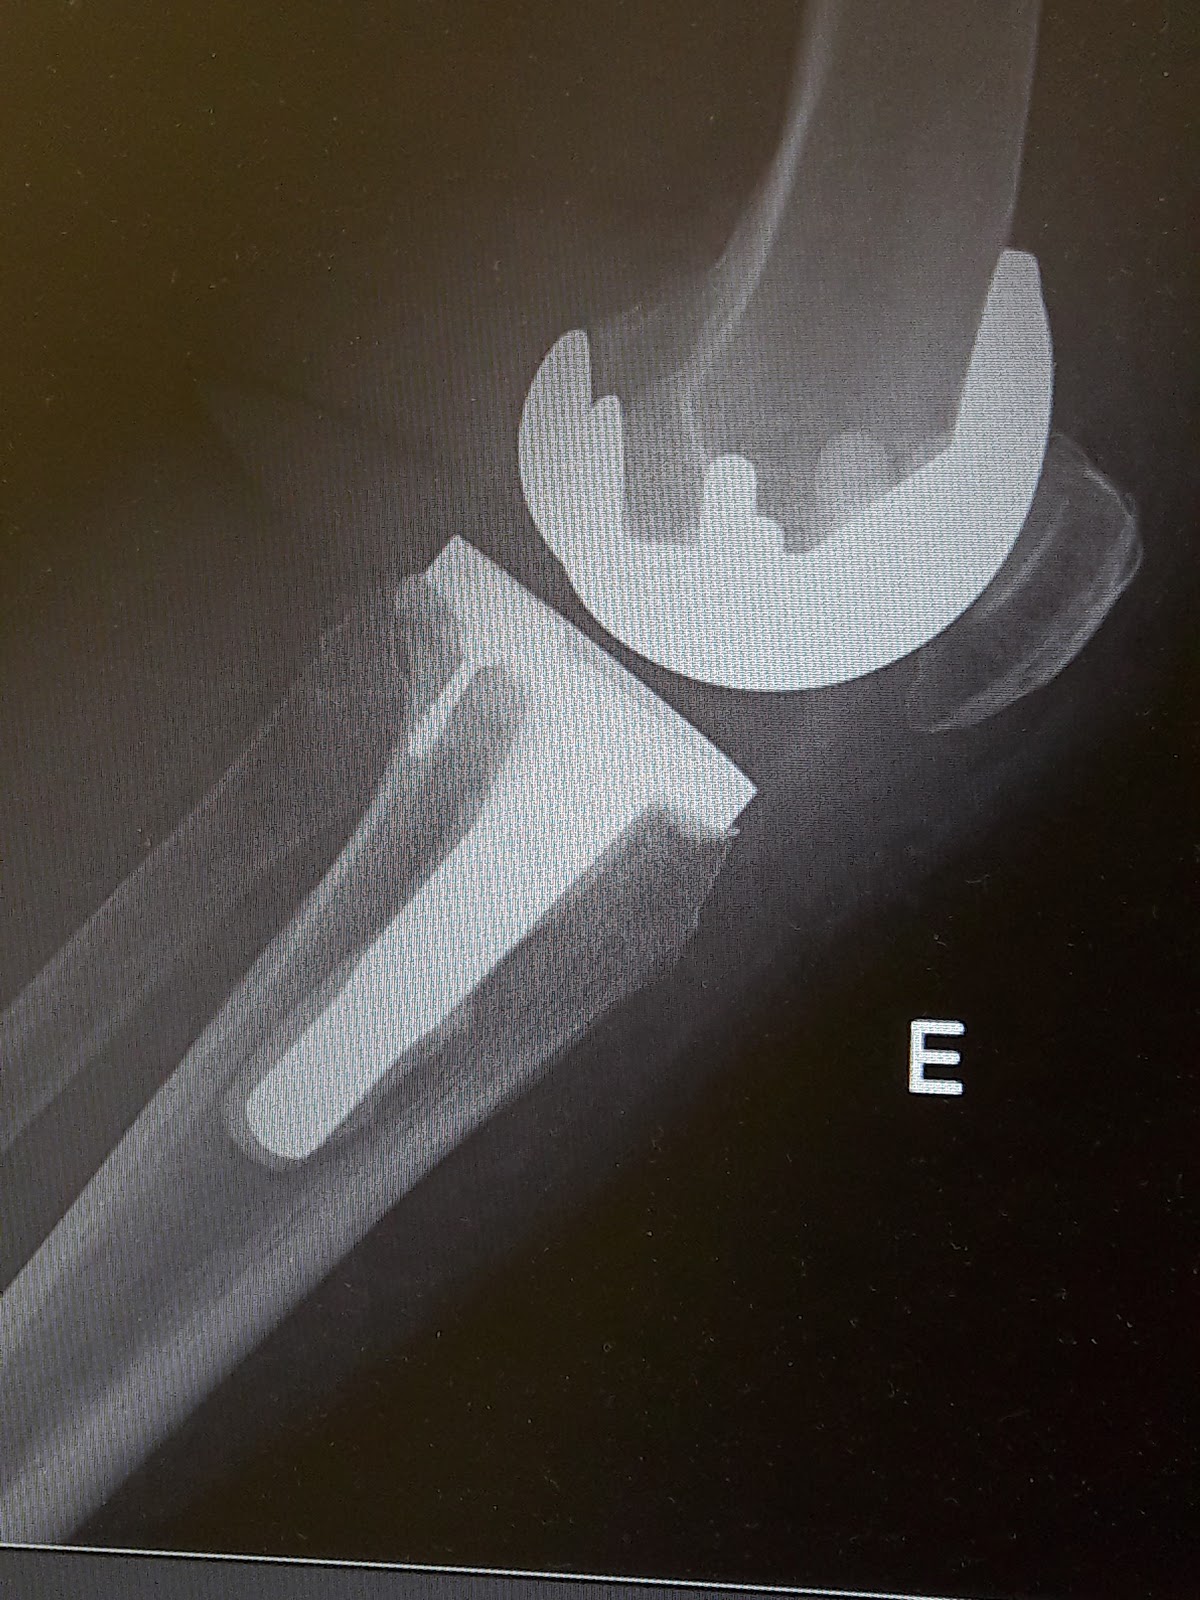

O dia continuou calmo, fui ajudar a mãe a tomar banho, limpei -lhe a casa e ás 16 horas fomos à consulta de Ortopedia ao Hospital. Fazer radiografia ao joelho que a médica se tinha esquecido de mandar fazer, como a mãe levava penso, marcar enfermagem, enfim andar de um lado para o outro, mas a médica disse que tudo estava bem, largar as canadianas, fazer a vida normal a única coisa que não deve fazer é NÃO CAIR. Pediu-nos desculpa de ter feito uma costura muito feia na perna da mãe, não percebe como a fez tão feia, não é seu hábito, ainda nos rimos. Mostrou-me a radiografia da mãe e pedi-lhe para tirar foto, ela deixou e disse-me para fazer publicidade a ela, não, não, diga antes que no Serviço Nacional de Saúde se fazem coisas como esta, e eu também quero referir o nome desta médica que se tem mostrado óptima, Drª Glória Magalhães.

O parafuso e o ferro mais comprido, não são bem os de uma prótese normal, a minha mãe tinha uma fractura que fez com que se tivesse que improvisar um pouco, isto para mim é uma

verdadeira obra de arte.